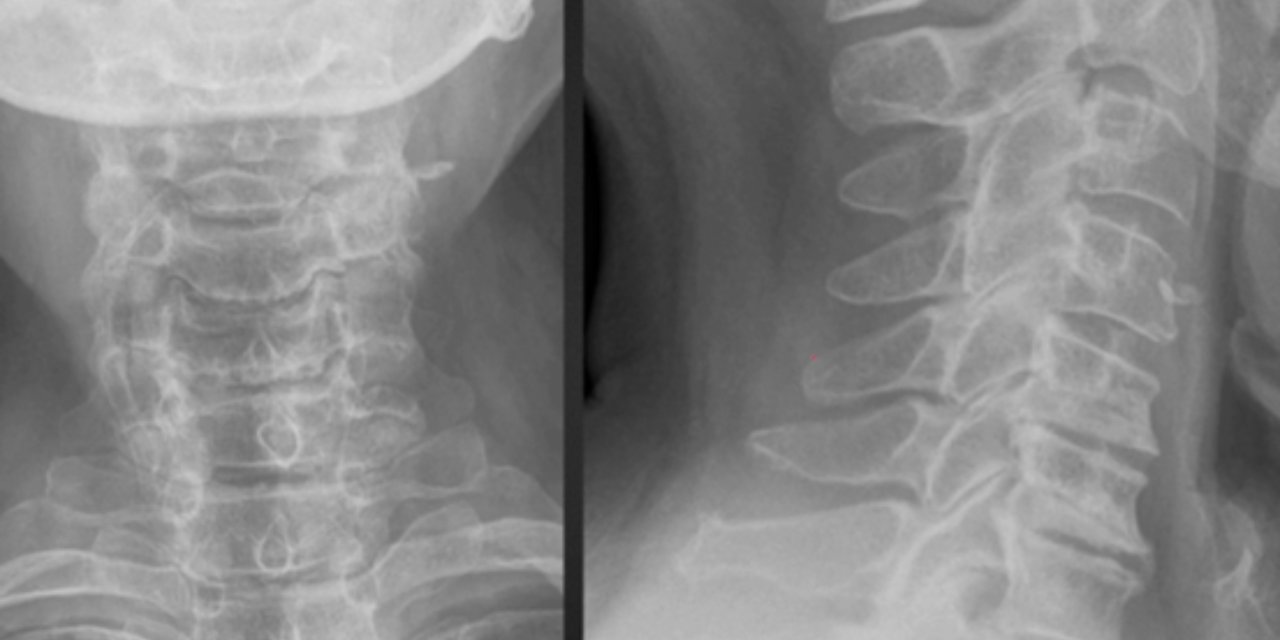

1. The Pseudofracture Appearance of Uncovertebral Arthrosis

In the lateral view of figure 1, note the horizontal radiolucent line through C5 and C6. This finding is often mistaken for a fracture on radiographs. The AP radiograph nicely demonstrates uncinate process hypertrophy at C6 and C7. The degenerative hypertrophy of the uncinate processes causes an abnormal pseudoarthrosis to form between the uncinate process below and the inferior vertebral body above. This pseudoarthrosis results in the horizontal radiolucency seen traversing the vertebral body.